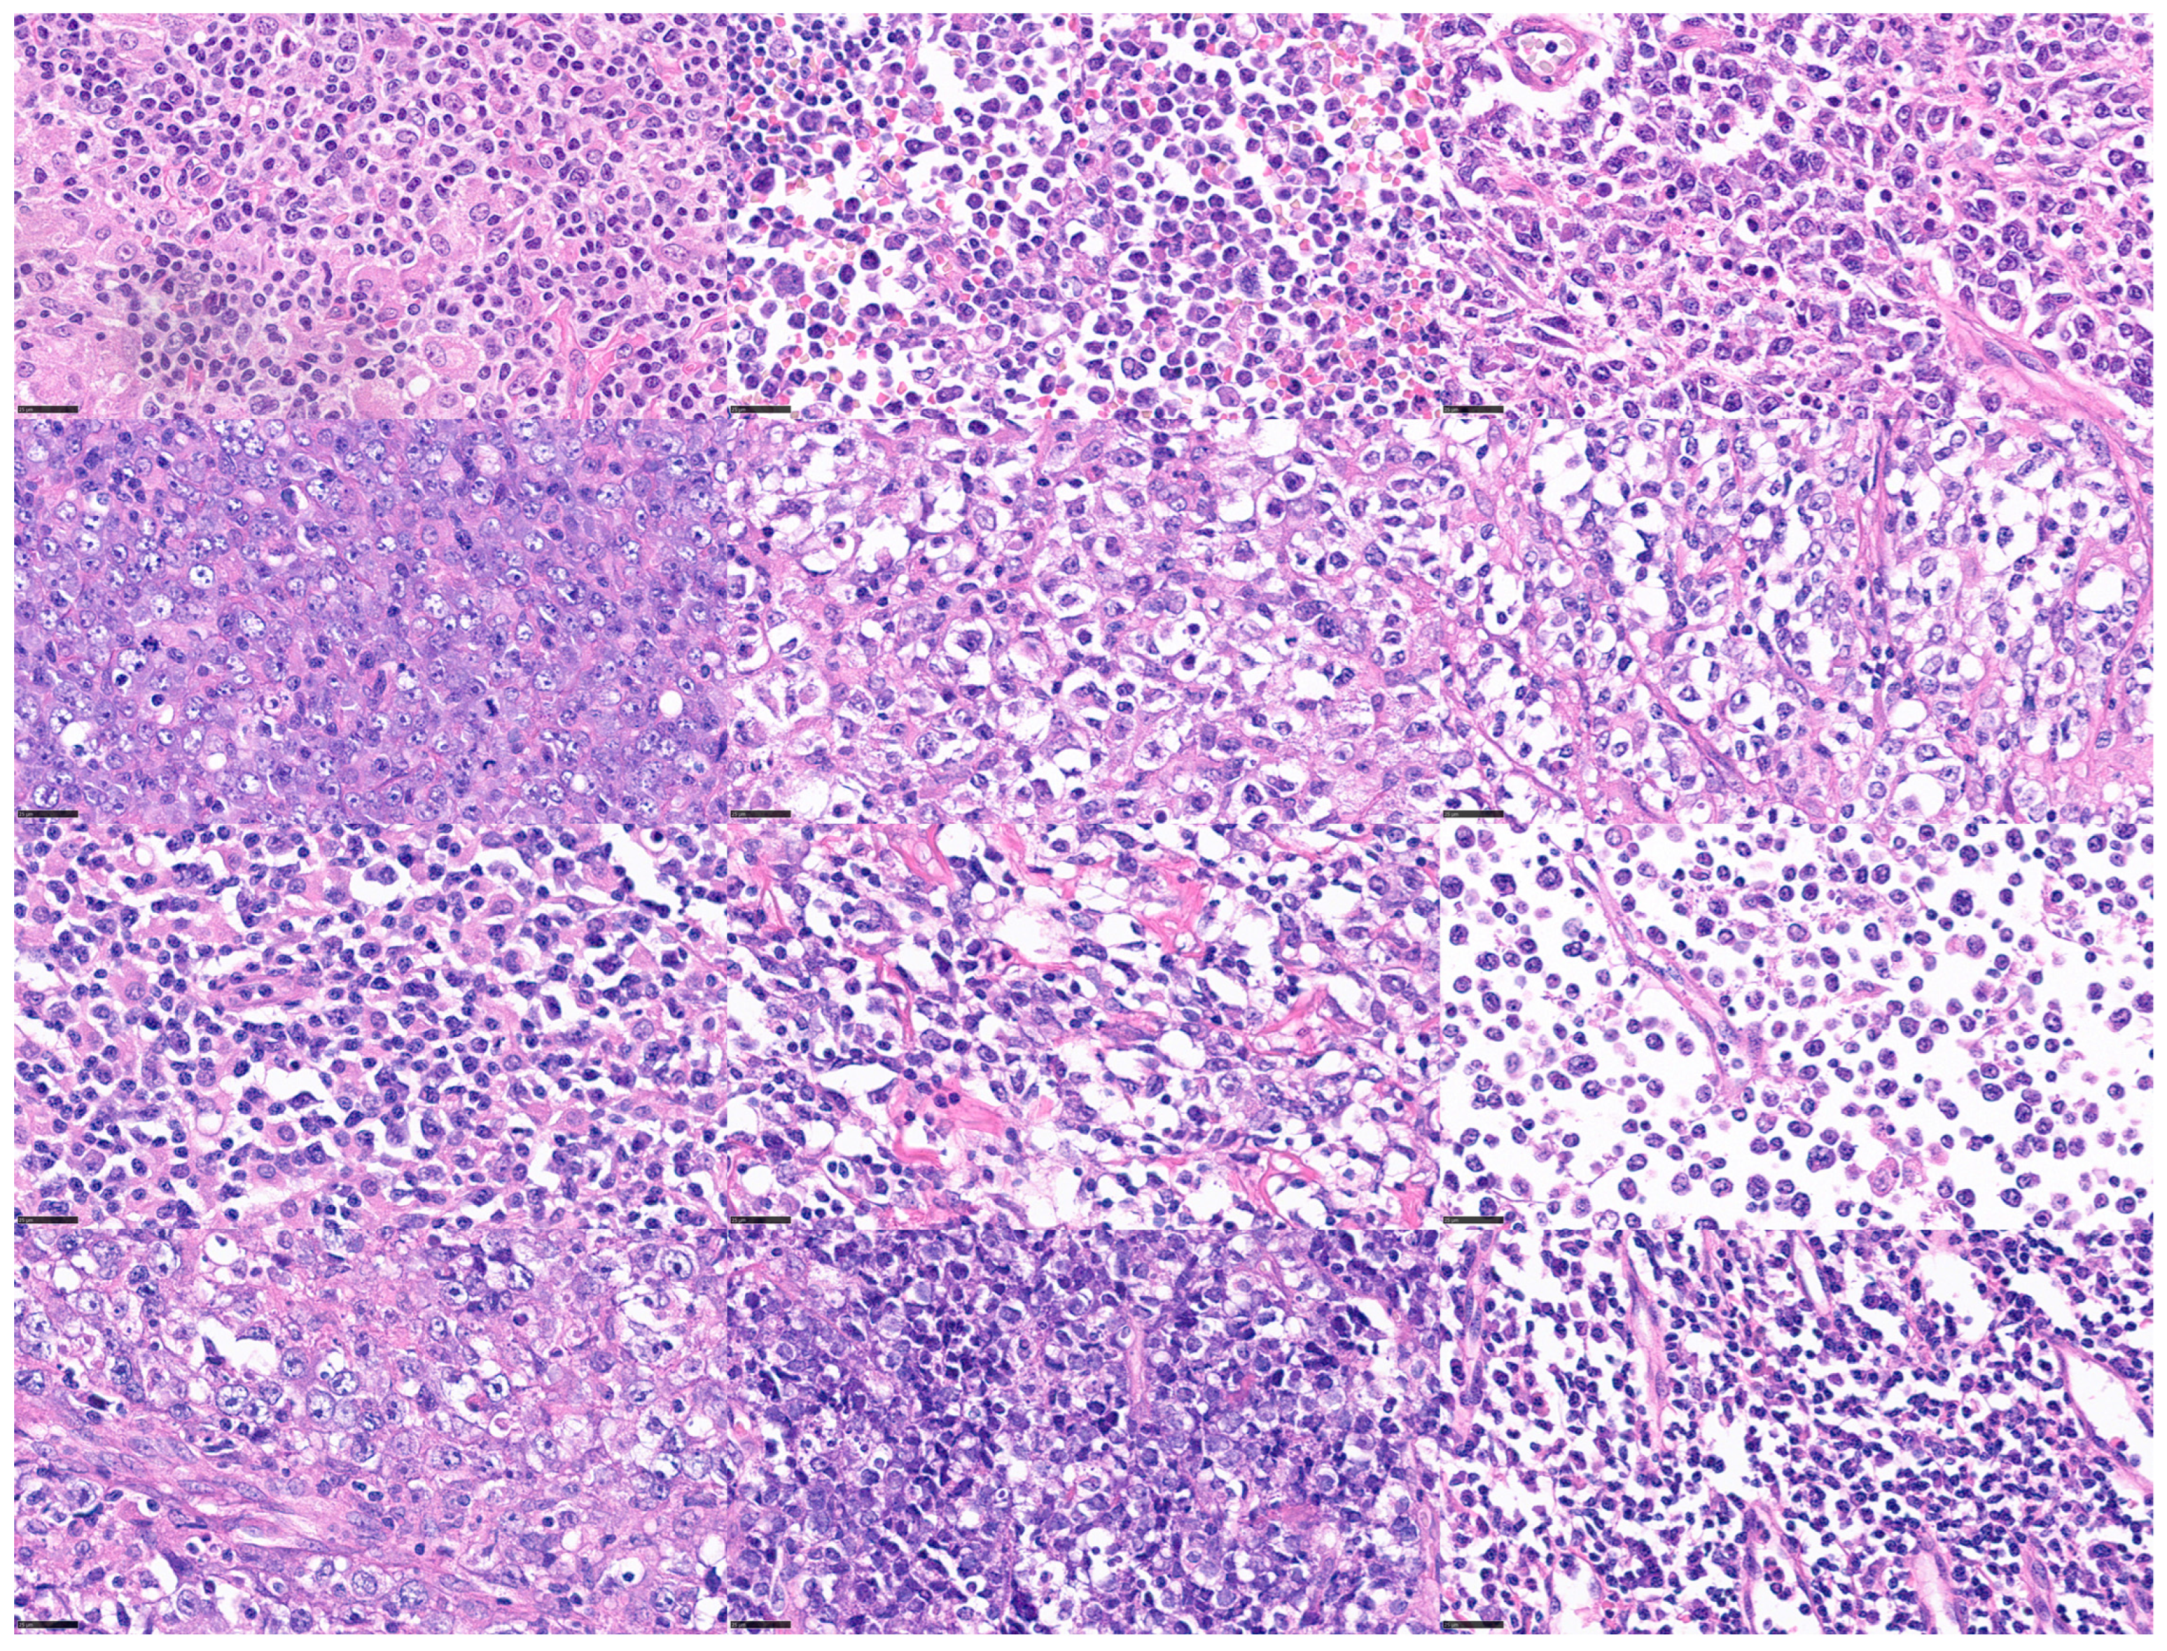

This histological variability of DLBCL is shown in Figure 3.

Diffuse large B-cell lymphoma (DLBCL) is one of the most frequent non-Hodgkin lymphomas and mature B-cell hematological neoplasms. DLBCL is not a single disease but a group of different diseases that differ in terms of morphological, genetic, and clinical characteristics [1,3]. There are several morphological subtypes, such as centroblastic, immunoblastic, and anaplastic, but their identification by histopathologists suffers from reproducibility. There are other phenotypic variants, such as the CD5 positive, MYC positive, and BCL2 positive, which tend to be associated with a poor prognosis [1,2,3,69,70,71,72].

Figure 3. Histological variability of diffuse large B-cell lymphoma (DLBCL). DLBCL is one of the most frequent mature B-cell neoplasms. DLBCL is a heterogeneous disease with differentmorphologic, genetic, and biologic characteristics. scale bar = 25 μm.